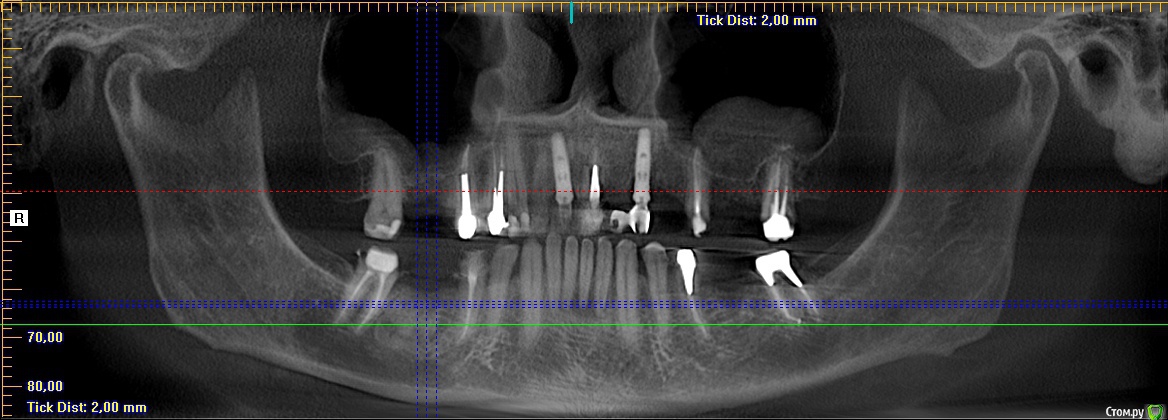

Тимур86 Опубликовано 5 ноября, 2019 Автор Поделиться Опубликовано 5 ноября, 2019 Не стоит бороться со своими желаниями... я бы удалил и гисту провёл, а потом можно и астру думаешь оно инкапсулированное? Мне кажется это типа остеомы, хотел забрать трепаном перед подготовкой ложа и на гистологию Ссылка на комментарий

red_butler Опубликовано 5 ноября, 2019 Поделиться Опубликовано 5 ноября, 2019 думаешь оно инкапсулированное? Мне кажется это типа остеомы, хотел забрать трепаном перед подготовкой ложа и на гистологиюДа, вроде капсула есть 1 Ссылка на комментарий

Тимур86 Опубликовано 5 ноября, 2019 Автор Поделиться Опубликовано 5 ноября, 2019 Ну вот на панораме вроде есть, а на срезах не сказать Ссылка на комментарий

Bier Опубликовано 5 ноября, 2019 Поделиться Опубликовано 5 ноября, 2019 а анамнез какой? может это биоосс в кисте? Ссылка на комментарий

Тимур86 Опубликовано 1 октября, 2020 Автор Поделиться Опубликовано 1 октября, 2020 Есть похожая ситуация! Но тут сложнее :глубже, и в непосредственной близости с нервом... У кого какие мысли? Ссылка на комментарий